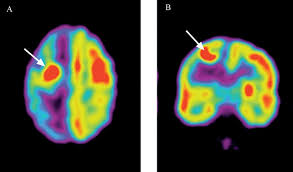

- Tomografía por emisión de positrones (PET): que se centra en los procesos bioquímicos de las células tumorales que son captados por una cámara tras el suministro de radiofármacos que permiten detectar las células tumorales. Esta prueba se podría complementar con las explicadas anteriormente.

- SPECT: se trata de la tomografía por emisión de fotón único, la cual permite un análisis funcional que informa el grado de afectación del tumor y sirve de gran ayuda en el diagnóstico y seguimiento de la enfermedad.